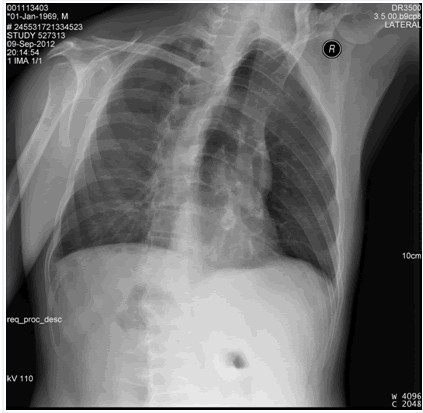

后肋骨折

圖示為右側(cè)3,5,6,7,8后肋骨折。

(1)后前位

(2)斜位